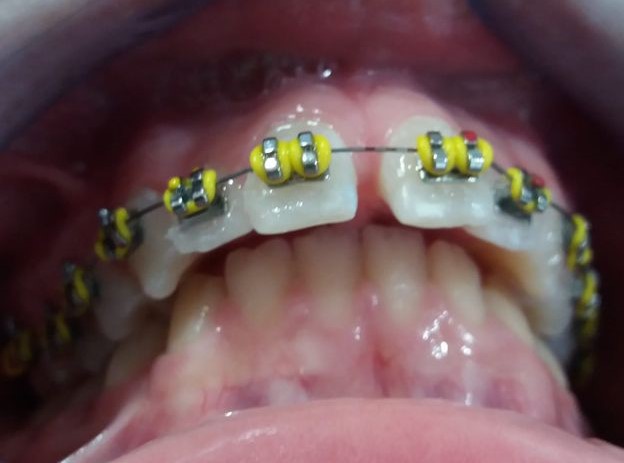

El tratamiento que se propone es alineamiento dental y estimular un desarrollo o crecimiento mandibular con algo que estimule dicho crecimiento. Este “algo” son los “aparatos funcionales” que actúan como si fueran poderosos músculos que tienden a empujar o estirar (según se diseñe) las estructuras dento-óseas de forma que estimula su crecimiento, siendo, que por su edad, está en época de máximo crecimiento. La mandíbula es un hueso capaz de crecer hasta los 25 años si se la estimula correctamente. Este aparato funcional es una especie de “jumper” o “saltador” o “empujador” que empuja el maxilar superior hacia atrás y empuja la mandíbula hacia delante aprovechando la fuerza de cierre de la arcada dental. Se lleva durante seis meses más o menos y el paciente no se lo puede quitar, es por esto que en realidad funciona tan rápido.

Recordamos que los músculos de la cara son los arquitectos de los huesos faciales, en este caso el aparato funcional, que es como un músculo, actúa para bien. Trascurrido este tiempo el paciente lleva elásticos de cierre para cerrar espacios dentales y resto de ajustes oclusales. Posteriormente a la retirada del aparato de ortodoncia el paciente lleva retenciones fijas y removibles durante la noche que garanticen el resultado en cuanto a recidivas.